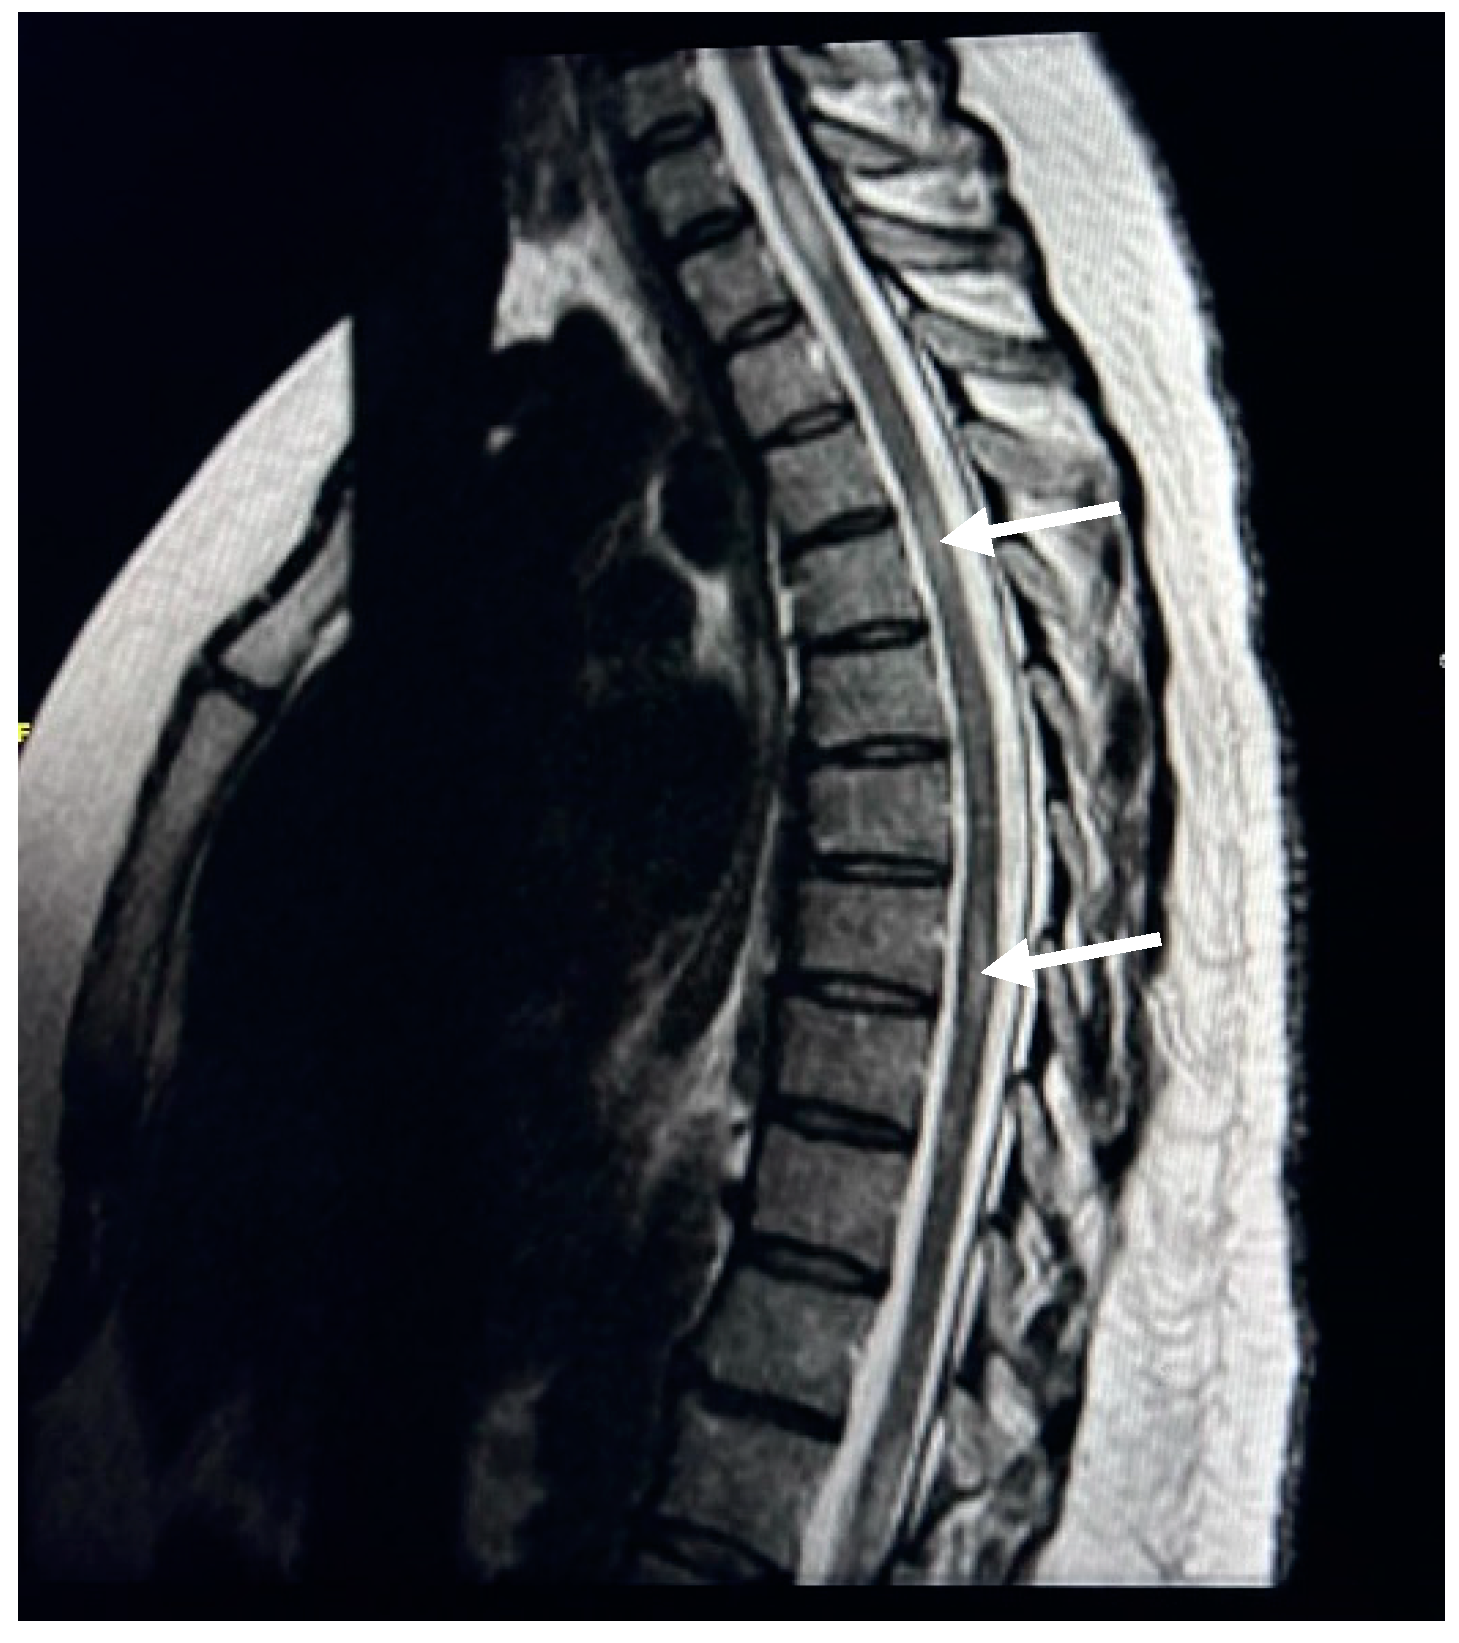

Exploring Spinal Cord Changes in Multiple Sclerosis Patients Using MRI